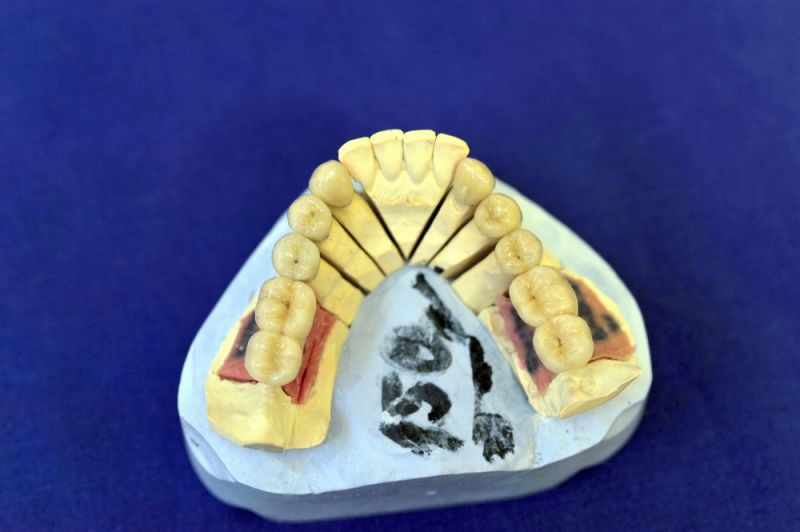

Mit dem heutigen Tag geht eine der technisch schwierigsten und anspruchsvollsten Arbeiten zu Ende, die im CMD-CENTRUM-KIEL jemals erstellt worden ist. Dabei sind es nur 10 Kronen, die benötigt werden, um die starken Kopf- und Gesichtsschmerzen der Patienten zu beseitigen.

Die Lösung einer Vielzahl technischer Probleme, die vorrangig verursacht waren durch:

4. Notwendigkeit die Mundhygienefähigkeit der Arbeit auch unter sehr beengten Verhältnissen zu schaffen, um der Arbeit eine günstige Prognose mitzugeben.

1. Notwendigkeit eines professionellen regelmäßigen Recalls, alle drei Monate

2. Notwendigkeit der Intrerdentalraumhygiene. Zwischen den Zähnen einmal pro Tag. Zwischen den Implantataufbauten zweimal pro Tag.